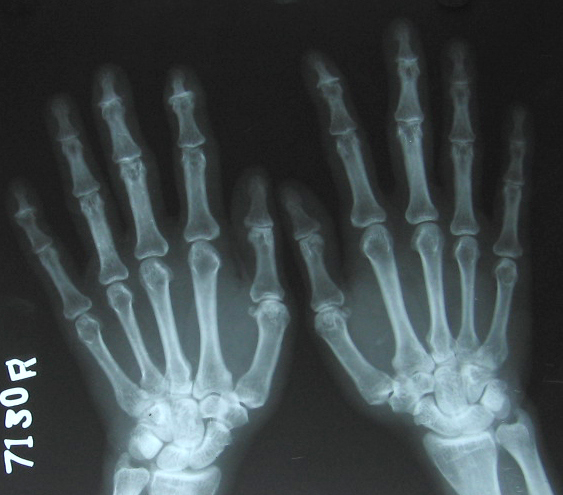

psoriasis hand A P c2

Fig.1 Both hands P.A view